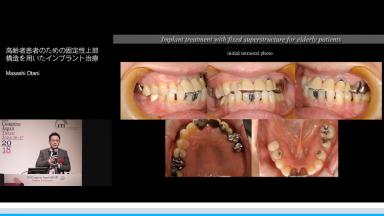

高齢者患者のための固定性上部構造を用いたインプラント治療

Masashi Otani

咀嚼機能の回復による栄養摂取は,オーラル・フレイル予防の点から重要である.無歯顎の高齢患者に対して,下顎位の設定という観点からインプラント支持型上部構造を提供する際の理論と実際を提供する.